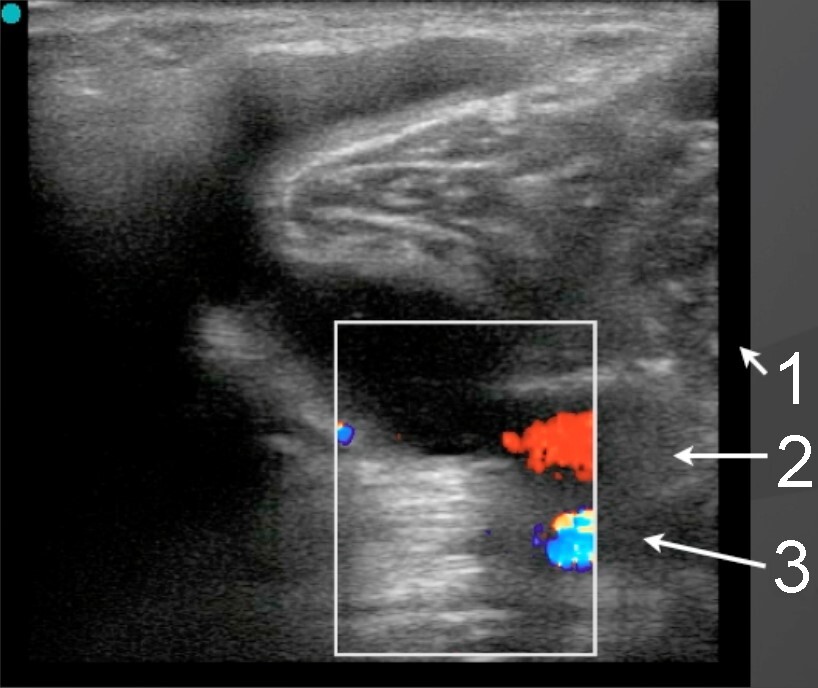

Knee Baker’s Cyst Anatomy Identification with Color Doppler Image

1. Femoral Nerve

2. Femoral Vein

3. Femoral Artery